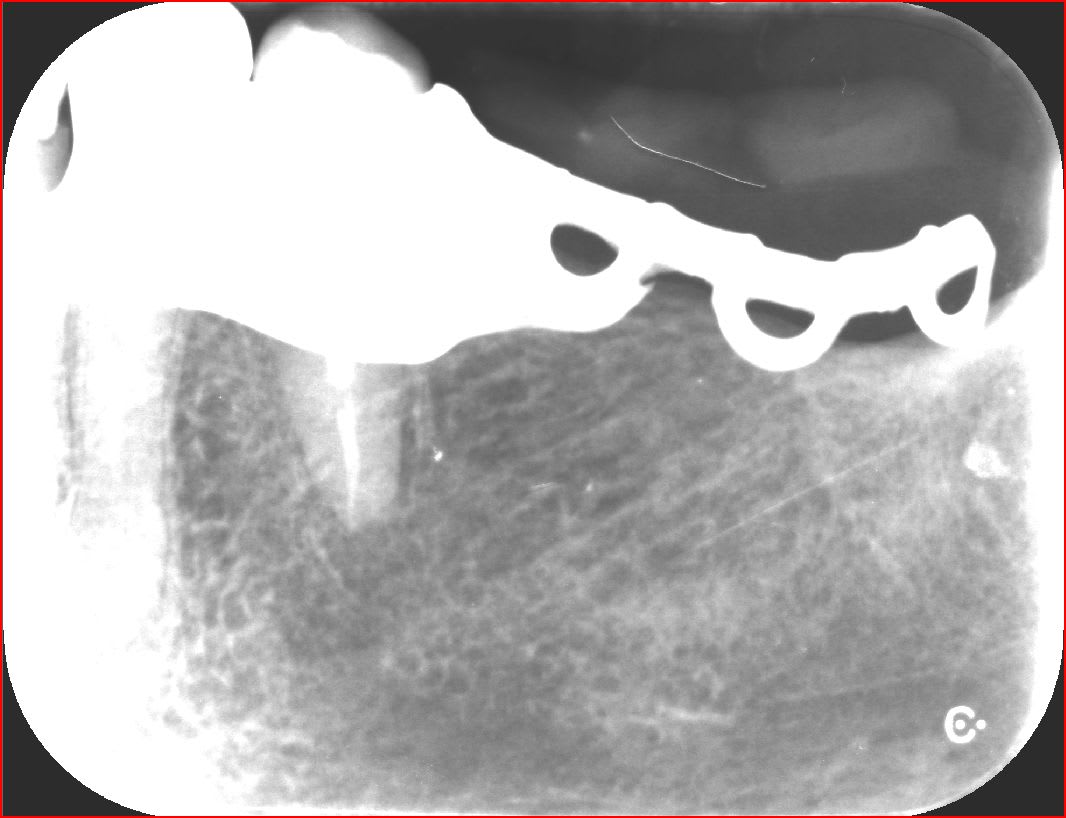

radio de controle de la pm qui avait prermis faire à la fois : - une elongation coronnaire ( de la dent et non par perte d'os bien sur )

- et un rajout d'os par fabrication naturelle d'os pres du nerf dentaire inf .

ç est la 1ere fois que l'on envisage de rajouter de l'os par le bas et non pas par le haut . ouais quand meme :-))))

bref finalement ,cette dent unitaire supporte un crochet de stellite depuis .je vous rappelle que ç est une 35 edentation terminale .

Eri zxwa2f - Eugenol

mg 0896 bimvru - Eugenol